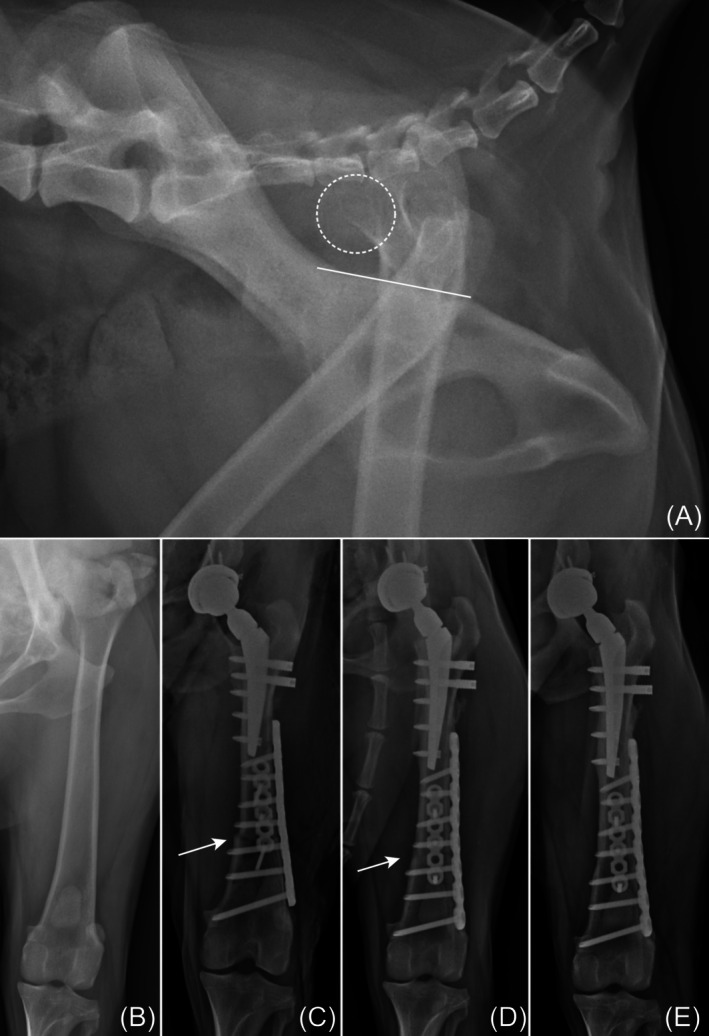

Methods: Standard THR was performed to alleviate pain and restore limb function. After confirming the prostheses were non-reducible, DFSO was performed as a novel tension-relieving technique at a level that allowed internal fixation. The shortening length was determined by the intraoperative tension required to reduce and maintain the prosthesis. Data from medical records were collected, including signalment, clinical signs, implant used, shortening length, and outcomes.

Results: Following DFSO, prosthesis reduction was successful in all dogs. The median femoral shortening length ratio was 13.8% (range, 10.7%-15.3%). One intraoperative complication involved a fissure of the greater trochanter, which occurred during trial reduction before DFSO. Median duration of follow-up was 21 months (range, 3-34 months). Two dogs showed good to excellent limb function. Bone union was consistently achieved in all DFSO procedures. Two postoperative complications were observed: one case of prosthesis luxation and one case of aseptic stem loosening. The owner declined revision surgery for luxation, and explantation was performed for the stem loosening.

Conclusion: DFSO could effectively manage irreducible prostheses in dogs with luxoid hips when conventional methods fail. However, careful case selection and meticulous surgical planning were essential to avoid complications.